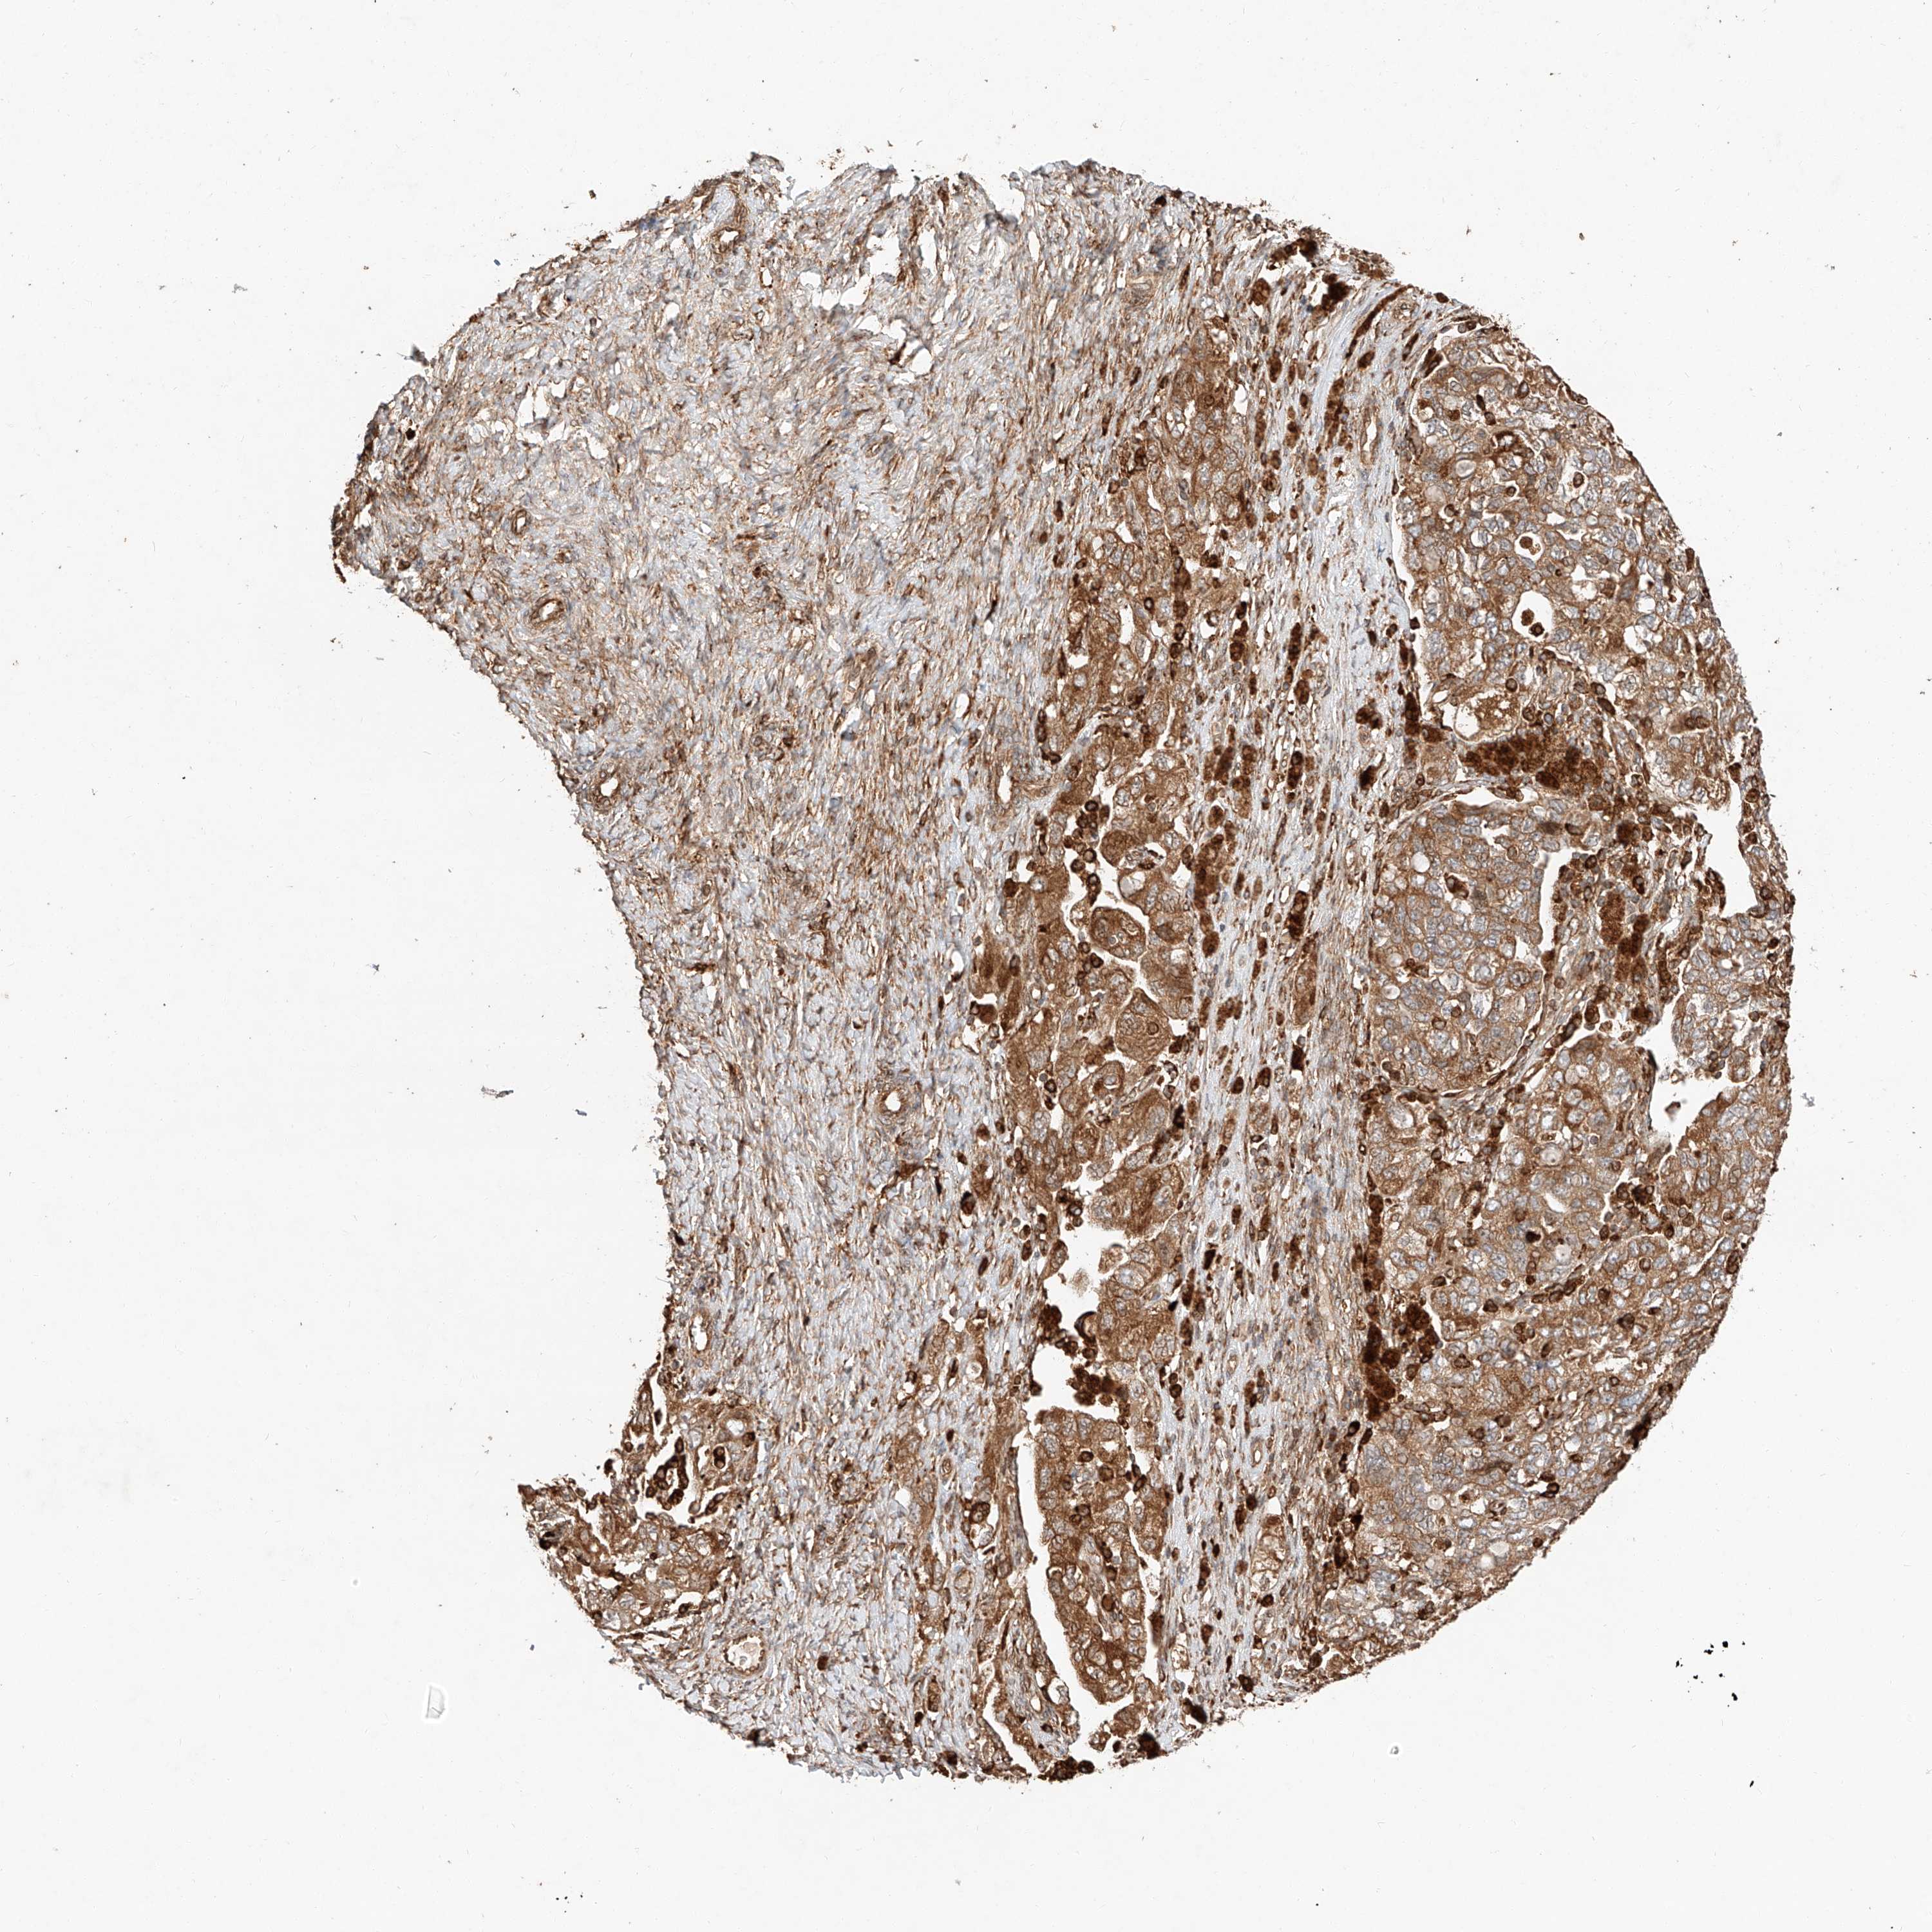

OVARIAN CANCER - Protein expressioni

A mouse-over function shows sample information and annotation data. Click on an image to view it in a full screen mode. Samples can be filtered based on level of antibody staining by selecting one or several of the following categories: high, medium, low and not detected. The assay and annotation is described here.

Note that samples used for immunohistochemistry by the Human Protein Atlas do not correspond to samples in the TCGA dataset.

Antibody stainingi

Antibody staining in the annotated cell types in the current human tissue is reported as not detected, low, medium, or high, based on conventional immunohistochemistry profiling in selected tissues. This score is based on the combination of the staining intensity and fraction of stained cells.

Each image is clickable and will lead to virtual microscopy that enables deeper exploration of all samples and also displays staining intensity scores, fraction scores and subcellular localization as well as patient and tissue information for each sample.

Antibody HPA028860

Staining

High

Medium

Low

Not detected

Intensity

Strong

Moderate

Weak

Negative

Quantity

>75%

75%-25%

<25%

None

Location

Nuclear

Cytoplasmic/membranous

Cytoplasmic/membranous,nuclear

Cystadenocarcinoma, serous, NOS

Carcinoma, endometroid

Cystadenocarcinoma, mucinous, NOS

Carcinoma, NOS